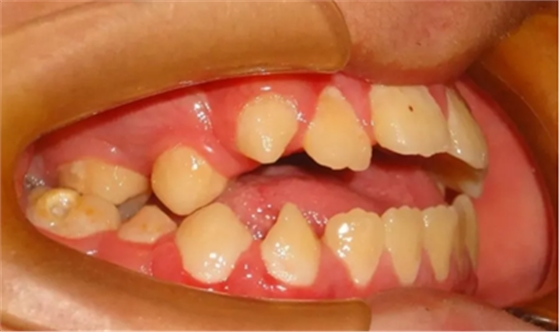

04 開合

因經(jīng)常吃不了瓜子,口腔不能執(zhí)行撕咬的動作或食物咬不斷前來就診,該如何避免?